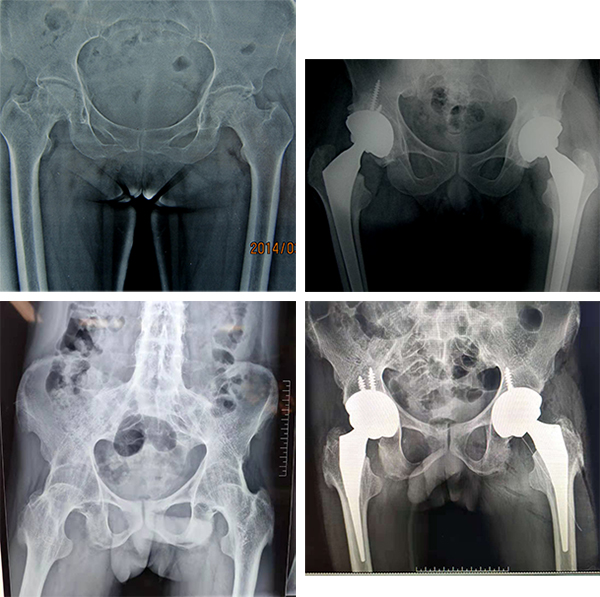

4、髋关节置换技术

1995年率先在豫西地区开展人工股骨头置换、全髋关节置换术治疗股骨颈骨折、股骨头缺血性坏死、髋臼发育不良等,尤其是进入本世纪初期,技术更加成熟,在豫西地区率先开展微小切口人工髋关节置换术,切口仅8cm左右,组织损伤轻,手术时间短,术后即可下床行走,功能恢复快,感染机会发生少。现已熟练掌握并常规开展人工髋关节置换术,尤其对一些复杂的、高难度的髋关节置换及翻修手术(如类风湿性关节炎、强直性脊柱炎晚期畸形的手术治疗)有自己丰富的临床经验。